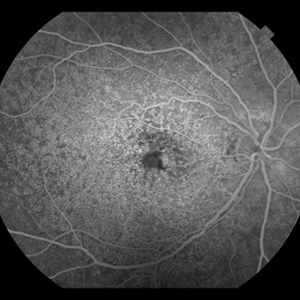

Sickle Cell Retinopathy with Sea Fans (angiography)

Fluorescein angiography (early/mid phase) of a 40-year-old man with African heritage and sickle SC disease. Sea fans are present temporal to the macula (leaking fluorescein).

Photographer: Geoffrey G. Emerson, MD, PhD, Retina Center, Minneapolis

Condition/keywords: sea fan, sickle cell retinopathy